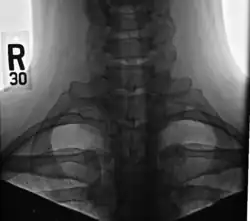

Bilateral, symmetric, full, ossified cervical ribs.

On imaging, cervical ribs can be distinguished because their transverse processes are directed inferolaterally, whereas those of the adjacent thoracic spine are directed anterolaterally.[16]